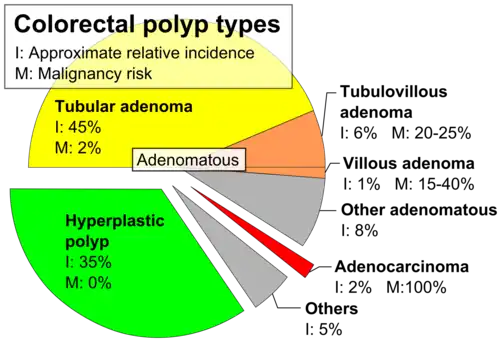

Colorectal polyps are often classified by their behaviour (i.e. benign vs. malignant) or cause (e.g. as a consequence of inflammatory bowel disease). They may be benign (e.g. hyperplastic polyp), pre-malignant (e.g. tubular adenoma) or malignant (e.g. colorectal adenocarcinoma).

Colorectal polyps can broadly be classified as follows:

- hyperplastic,

- neoplastic (adenomatous and malignant),

- hamartomatous and,

- inflammatory.

| Type | Risk of containing malignant cells | Histopathology | Image | |

| Hyperplastic polyp | 0% | No dysplasia.[10]

| Tubular adenoma | 2% at 1.5 cm[12] | Low to high grade dysplasia[13] | Over 75% of volume has tubular appearance.[14] |

| Tubulovillous adenoma | 20% to 25%[15] | 25–75% villous[14] |

| Villous adenoma | 15%[16] to 40%[15] | Over 75% villous[14] | .jpg)

| Sessile serrated adenoma (SSA)[17] |

| Colorectal adenocarcinoma | 100% |

The common adenomas of the colon (colorectal adenoma) are the tubular, tubulovillous, villous, and sessile serrated (SSA).[18] A large majority (65–80%) are of the benign tubular type with 10–25% being tubulovillous, and villous being the most rare at 5–10%.[9]

The villous subdivision is associated with the highest malignant potential because they generally have the largest surface area. (This is because the villi are projections into the lumen and hence have a bigger surface area.) However, villous adenomas are no more likely than tubular or tubulovillous adenomas to become cancerous if their sizes are all the same.[18]

- Type of polyp (e.g. villous adenoma):

- Tubular adenoma: 5% risk of cancer

- Tubulovillous adenoma: 20% risk of cancer

- Villous adenoma: 40% risk of cancer